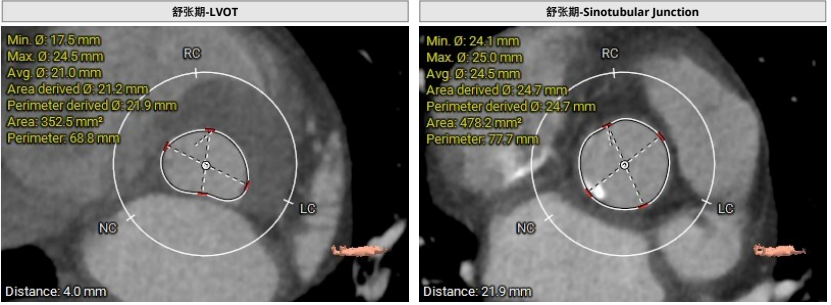

临床团队同时使用了Tavigator™进行术前影像学评估,配合医生手工描点评估。

主动脉瓣瓣上及瓣下多平面测量

患者为71岁女性。瓣环圆化直径21.8mm,Type0型二叶瓣,瓣叶增厚轻度钙化。左侧冠脉开口高度13.1mm,右侧冠脉开口高度13.8mm,并且STJ高度可以达到22.3mm。投照角度推荐LAO8度/CRA8度。可行18mm球囊前扩,考虑到环上锚定,推荐0位植入Xcor™-23瓣膜,酌情后扩。